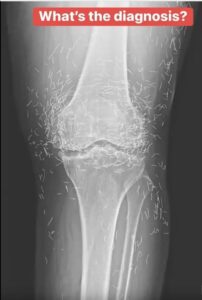

Years later, when doctors took X-rays to evaluate her knee condition, they weren’t prepared for what appeared on the images. Her knees were filled with dozens of bright, metallic flecks — tiny needles embedded deep within the joint area.

The findings were later documented in a case published by the New England Journal of Medicine.